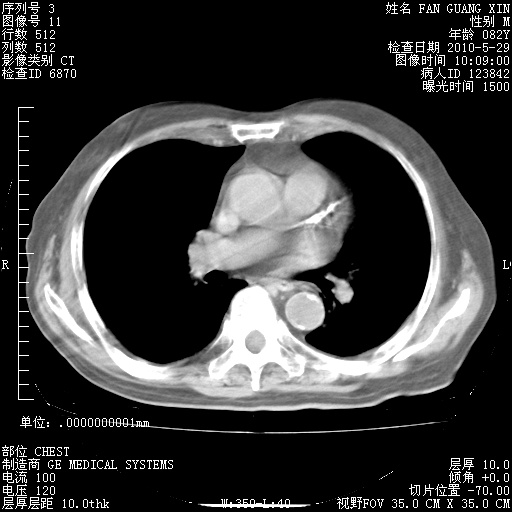

再治疗10天后的肺部CT

再治疗10天后的肺部CT 纵膈窗